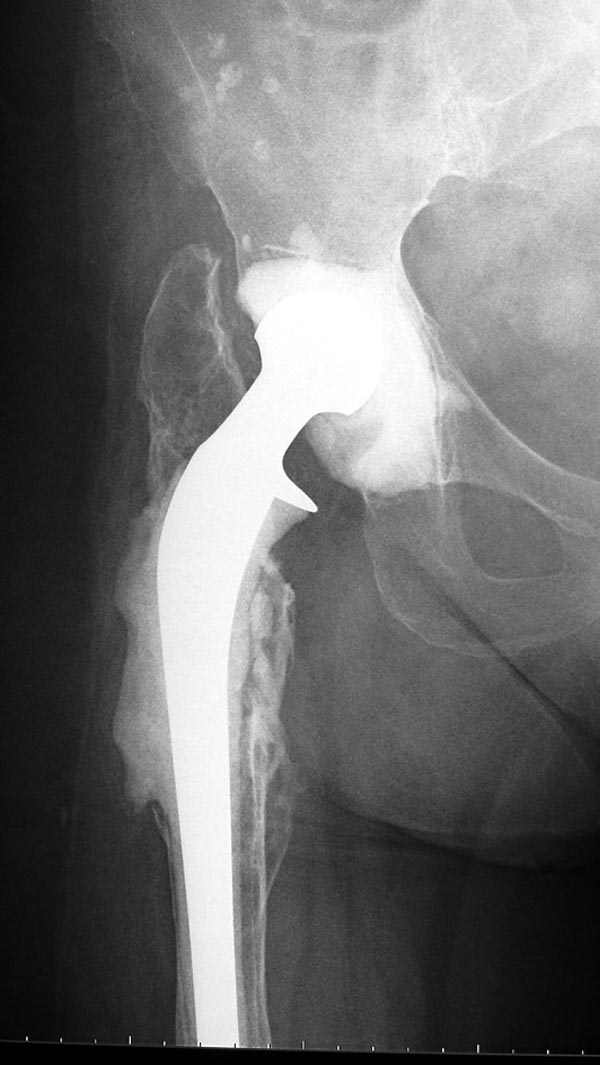

Из предложенных вариантов быстрейший результат можно ожидать после поэтапного эндопротезирования.

Полость вертлужной впадины и проксимальное бедро были заполнены custom made временным протезом из цемента.

В вертлужную полость устанавливается цемент и головкой протеза выдавливается выемка, т.е. создается место для головки. В проксимальное бедро устанавливается заранее подготовленный цементный бедренный компонент.

Через пару месяцев после улучшения мягкотканой

кондиции можно приступить к окончательному протезу.